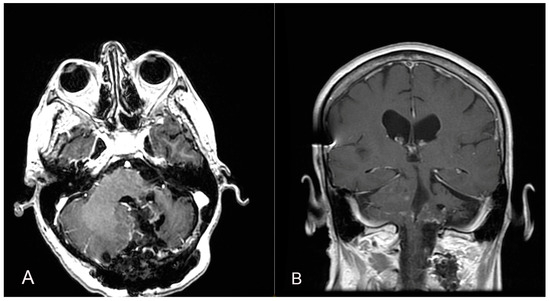

Figure 5.

A second surgery was performed through a telo-velar approach, and postoperative contrast-enhanced brain MRI (A,B) is shown. The lesion intraoperatively appeared to be a calcified mass tenaciously attached to contiguous structures, and a portion of the tumor was found to be tightly adherent to the left lateral recess, which was left in situ after a positive irritative response during the neurostimulation of the XII cranial nerve.